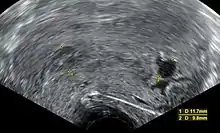

Ultrasound criteria

A review article in The New England Journal of Medicine based on a consensus meeting of the Society of Radiologists in Ultrasound in America (SRU) has suggested that miscarriage should be diagnosed only if any of the following criteria are met upon ultrasonography visualization:[97]

| Crown-rump length of at least 7 mm and no heartbeat. | Crown–rump length of less than 7 mm and no heartbeat. | [97][98] |

| Mean gestational sac diameter of at least 25 mm and no embryo. | Mean gestational sac diameter of 16–24 mm and no embryo. | [97][98] |

| Absence of embryo with heartbeat at least 2 weeks after an ultrasound scan that showed a gestational sac without a yolk sac. | Absence of embryo with heartbeat 7–13 days after an ultrasound scan that showed a gestational sac without a yolk sac. | [97][98] |

| Absence of embryo with heartbeat at least 11 days after an ultrasound scan that showed a gestational sac with a yolk sac. | Absence of embryo with heartbeat 7–10 days after a scan that showed a gestational sac with a yolk sac. | [97][98] |

| Absence of embryo at least 6 weeks after last menstrual period. | [97][98] | |

| Amniotic sac seen adjacent to yolk sac, and with no visible embryo. | [97][98] | |

| Yolk sac of more than 7 mm. | [97][98] | |

| Small gestational sac compared to embryo size (less than 5 mm difference between mean sac diameter and crown-rump length). | [97][98] |